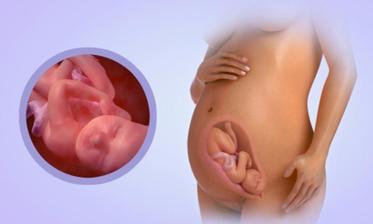

23.5. pro průkazku + odběr krve + utz 11+0 mimisek 4,2cm